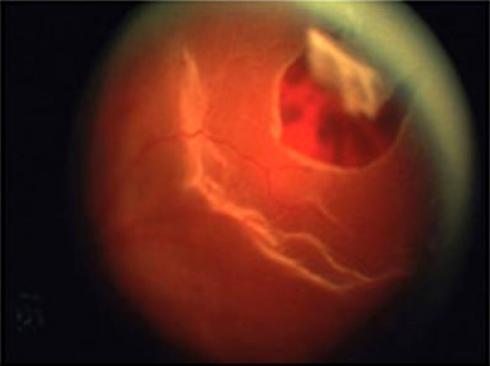

Desgarros Retinianos

La parte posterior del ojo contiene un gel llamado vítreo. El cuerpo vítreo esta casi en su totalidad con la retina. El gel vítreo experiment...